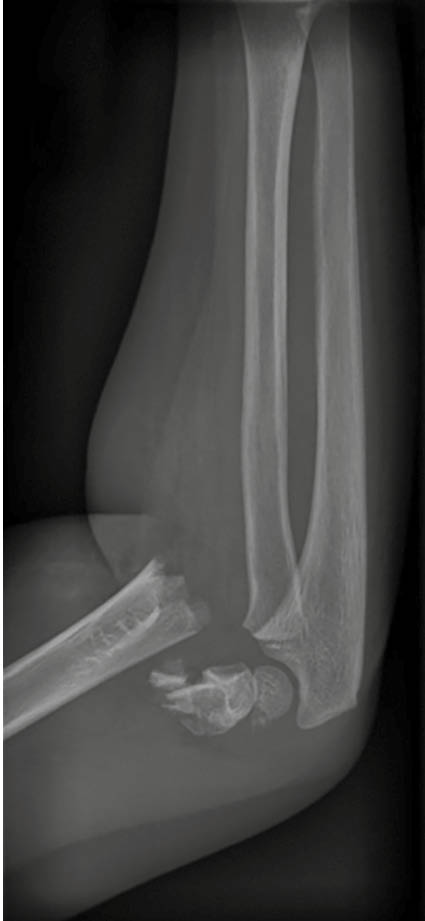

Aufgrund der symptomatischen Cholezystolithiasis nach stattgehabter akuter Cholezystitis wurde die Indikation zur elektiven laparoskopischen Cholezystektomie gestellt. An diagnostischen Verfahren wurden auswärts ein Angio-MRT (Abb. 1 – 4) des Oberbauches und eine Magnetresonanz-Cholangiopankreatikographie (MRCP) durchgeführt, welche eine Cholezystitis bei Cholezystolithiasis und eine beginnende Leberzirrhose nachweisen konnten. Im Rahmen der präoperativen Vorbereitung wurde eine Echokardiographie durchgeführt, in welchem eine Herzinsuffizienz infolge der Volumenbelastung durch die AV-Shunts i.R. des KMS und eine „Cirrhose cardiaque“ ausgeschlossen werden konnten. Als Marker einer intravasalen Gerinnungsaktivierung wurden erhöhte Prothrombinfragmente, D-Dimere und eine erniedrigte Antiplasmin-Konzentration sowie eine gesteigerte Fibrinolysekapazität detektiert. Eine sekundäre Thrombozytopenie oder eine Fibrinogen- und Faktor-XIII-Verminderung konnten ebenso wie das Vorliegen eines erworbenen von-Willebrand-Syndroms ausgeschlossen werden.

In einer hämostaseologischen Vorstellung wurde die Pausierung der Thrombozytenaggregationshemmung über 7 d unter „Bridging“ mittels niedermolekularem Heparin und eine medikamentöse Hemmung der Hyperfibrinolyse durch Tranexamsäure bis zum 3. postoperativen Tag bzw. in Abhängigkeit von Klinik und des hämostaseologischen perioperativen Monitorings empfohlen. Als perioperative Antibiotikaprophylaxe wurde Imipenem eingesetzt. Der Kameratrokar wurde entsprechend der aus dem Angio-MRT bekannten linksseitigen Ausprägung der Gefäßmalformationen (Abb. 1 – 4) in typischer Nabelposition platziert.